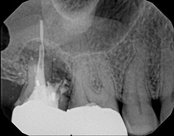

Upper molar failed root canal and apicoectomy:

Before

Immediately after

3-month follow-upThis person presented with one root that had failed from root canal treatment. The arrow in the picture, shows the infection as well as extra filling material that was pushed out of the root. An apical microsurgery was performed using the laser. The infection and excess material was cleaned out. Complete healing is visible 3 months after. The tooth was saved. This is a poor area for an implant.